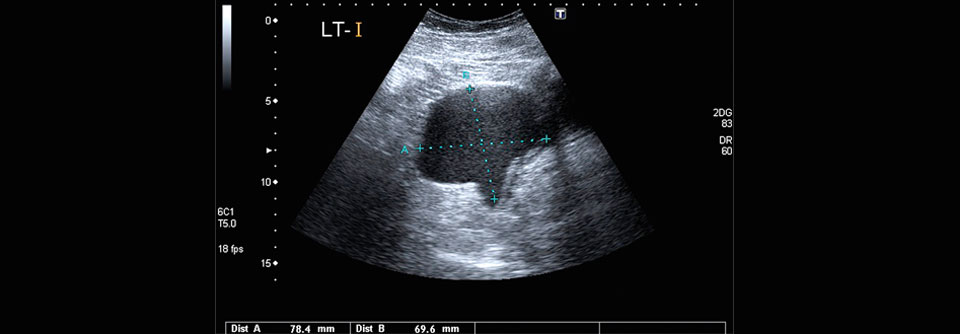

Klagen Ihre Patientinnen über wiederkehrende quälende Bauchschmerzen trotz unauffälligem gastroenterologischen Befund? Bei einigen von ihnen steckt vermutlich eine Endometriose dahinter. Bis diese diagnostiziert wird, vergehen oft mehrere Jahre.

Schätzungen zufolge ist etwa jede zehnte Frau im gebärfähigen Alter von Endometriose betroffen. Die Dunkelziffer ist hoch. Denn die damit assoziierten Beschwerden sind oft unspezifisch und können weit über das kleine Becken hinausgehen: Symptome wie bei einem Reizdarm oder einer Colitis ulcerosa, Migräne oder andere Arten von (chronischen) Schmerzen sind nur einige Beispiele. Und je länger die Erkrankung unerkannt bleibt, des­to geringer werden die Chancen für eine langfristig erfolgreiche Therapie, warnt das Team um Professor Dr. Krina­ Zondervan­ vom Endometriosis Care and Research Centre am Nuffield Department of Women’s and Reproductive Health der University of Oxford.